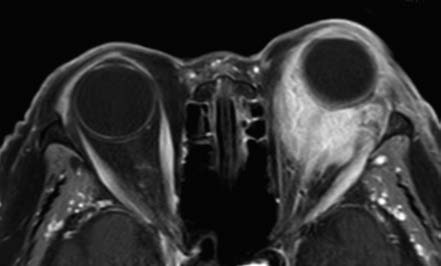

Figure 1 Imaging features of left orbital lymphoma

Contrast-enhanced axial T1-weighted MRI shows the tumor encasing the eyeball with a mold-like appearance and significant enhancement.

MRI typically demonstrates intermediate signal intensity on T1-weighted imaging (T1WI) and high signal intensity on T2-weighted imaging (T2WI), with marked enhancement on contrast imaging. When the tumor encases the eyeball, it may present with a mold-like appearance. Orbital lymphoma can be challenging to differentiate from benign conditions such as nonspecific orbital inflammatory disease; biopsy is often required for definitive diagnosis.